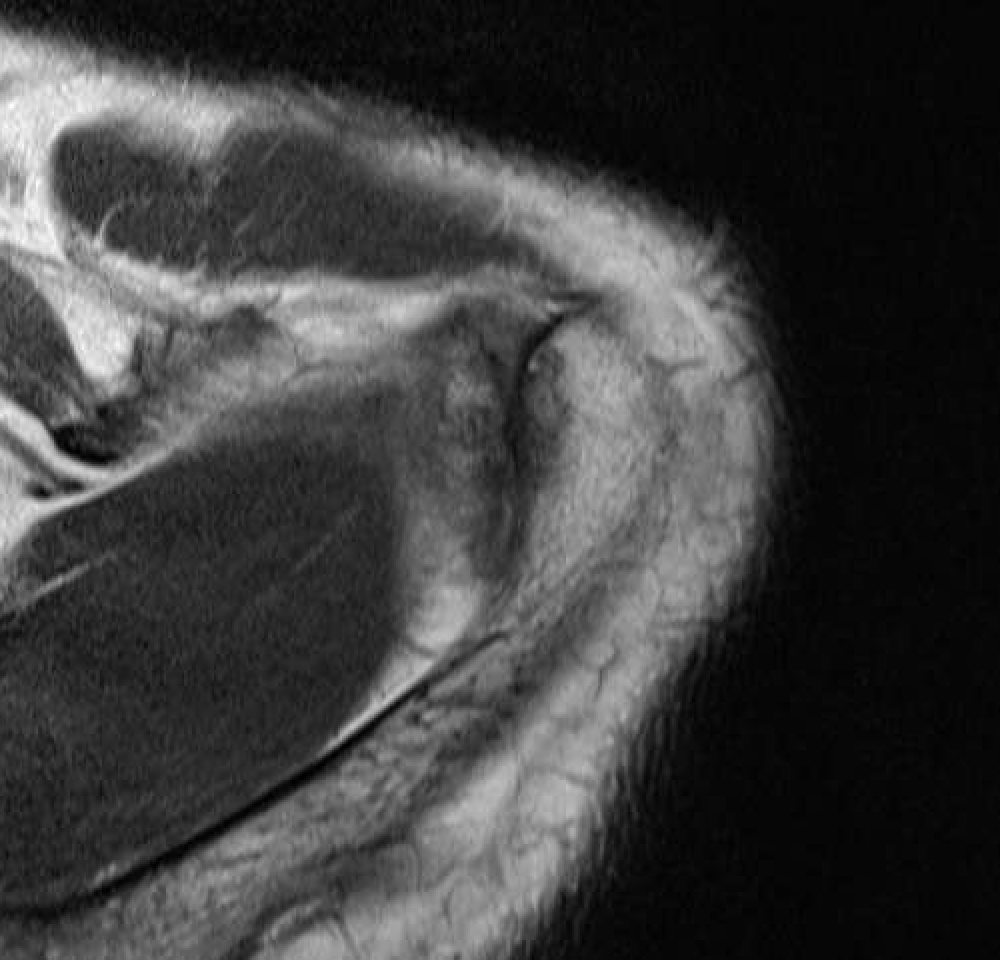

MRI

Acromioclavicular osteoarthritis

Stein et al. J Should Elbow Surg 2001

Grade I: Normal

Grade II: Capsular distension, bone marrow edema, mild joint narrowing

Grade III: Capsular distension, joint space narrowing, marginal osteophytes

Grade IV: Markedly abnormal ACJ with large osteophytes